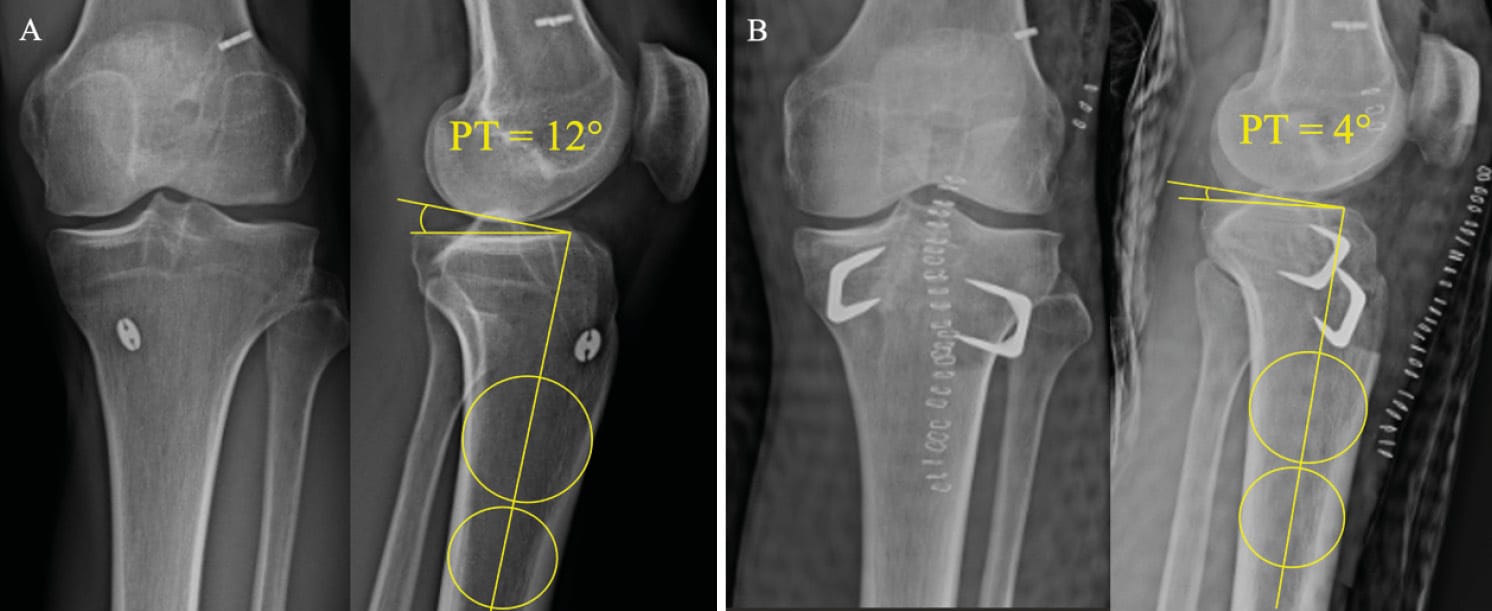

Radiology images should be obtained to include true lateral views showing 15 cm of proximal tibia with 20° of flexion in single-leg weight-bearing. The condyles will be aligned under fluoroscopy before the conventional radiography is performed. Any deviation from lateral will lead to distortions and the measurements will not be possible to interpret [14] Vieider RP, Mehl J, Rab P, Brunner M, Schulz P, Rupp MC, et al. Malrotated lateral knee radiographs do not allow for a proper assessment of medial or lateral posterior tibial slope. Knee Surg Sports Traumatol Arthrosc. 2024;32(6):1462–9. (Figure 1). Next, the technique for measuring the tibial slope must be chosen so that it is reproducible and can be compared from one study to another. It is crucial to choose one method and stick to it. The technique that uses the proximal anatomical tibial axis has a normal value of 9° of slope and the method is described in Figure 2 [15] Brazier J, Migaud H, Gougeon F, Cotten A, Fontaine C, Duquennoy A. Evaluation of methods for radiographic measurement of the tibial slope. A study of 83 healthy knees. Revue de chirurgie orthopédique et réparatrice de l’appareil moteur. 1996;82(3):195–200. . The normal value for SATT is 1.31 mm [16] Cance N, Dan MJ, Pineda T, Demey G, Dejour DH. Radiographic Investigation of Differences in Static Anterior Tibial Translation With Axial Load Between Isolated ACL Injury and Controls. Am J Sports Med. 2024 Feb 1;52(2):338–43. . If translation is posterior, the measurement will have a negative value. The measurement method is described in Figure 3.

The procedure to choose to directly address posterior tibial slope is tibial deflexion osteotomy. It is possible to perform a supra-tubercular, trans-tubercle or infra-tubercle deflexion osteotomy, as described above (Figure 7). The most important factor in choosing a technique is that the surgeon feels at ease using it, since there is currently no technique emerging as superior to any other and each one has its own advantages and drawbacks [29] Onishi S, Kim Y, Nakayama H, Mansour AA, Lowe WR, Ollivier M. Infratubercle Anterior Closing Wedge Osteotomy Corrects Sagittal Alignment without Affecting Coronal Alignment or Patellar Height. Journal of Clinical Medicine. 2024 Jan;13(16):4715. . We have set out the technique for the supra-tubercular osteotomy because this technique means that the resection can be made at the site of the deformity, in the metaphysis, in an area that is favourable to bone healing [30] Demey G, Giovannetti de Sanctis E, Mesnard G, Müller JH, Saffarini M, Dejour DH. Posterior tibial slope correlated with metaphyseal inclination more than metaphyseal height. Knee. 2023 Oct 1;44:262–9. . It has been clearly demonstrated that this osteotomy technique preserves sufficient metaphyseal bone for fixation [31] Demey G, Giovannetti de Sanctis E, Mesnard G, Müller JH, Saffarini M, Dejour DH. Sufficient Metaphyseal Bone for Wedge Removal and Fixation Hardware During Supratuberosity Tibial Deflexion Osteotomy in Knees With Excessive Posterior Tibial Slope. Am J Sports Med. 2023 Jul 1;51(8):2091–7. . The goal of this surgery is to obtain a tibial slope of between 4 and 6°, which means that SATT will be kept between 0 and 5mm without increasing the stresses on the posterior cruciate ligament (Figure 8).